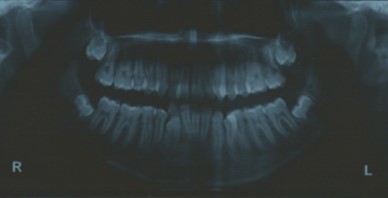

Radiographic assessment. The panoramic radiograph confirmed the presence of all permanent teeth with the presence of 18, 28, 38 and 48 tooth germs with normal alveolar bone levels. (Figure 2).

Figure 2.Pre-treatment panoramic radiograph